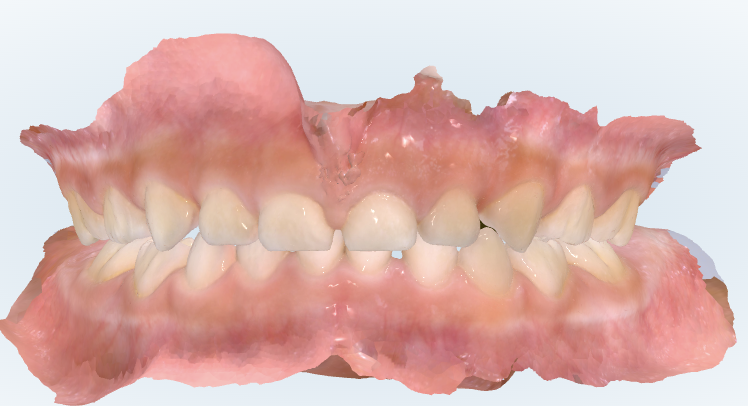

初診時の画像診断

上下の歯並びに隙間があります。上の前歯の間の筋もあります。

下の前歯の永久歯が乳歯の内側から生えてきています。